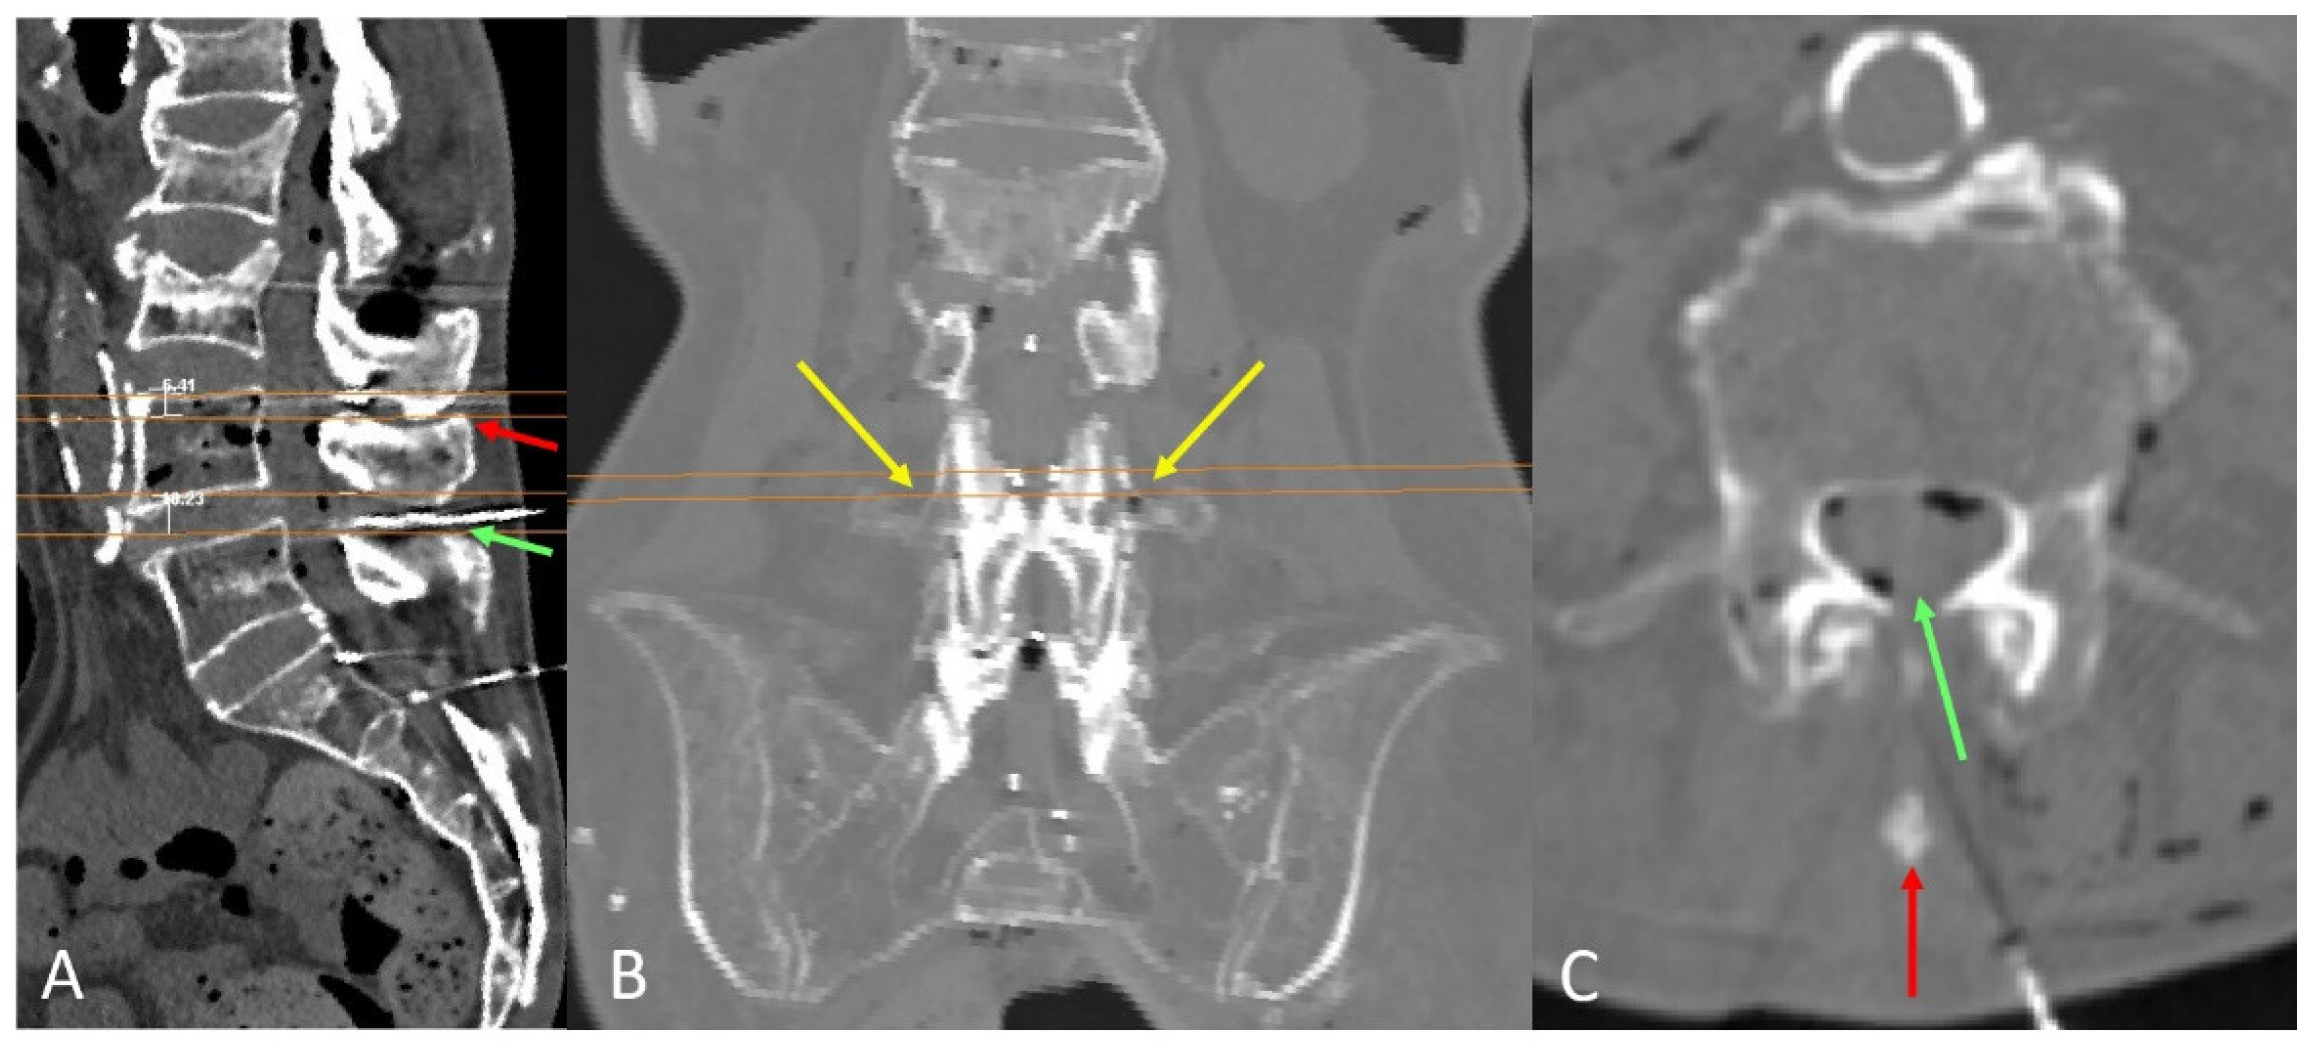

2.1.1. Transverse Process and Dural Sac Alignment

3.1. Transverse Process and Depth Level Within the Dural Sac

3.2. D Reconstruction, Transverse Process and Interlaminar Window